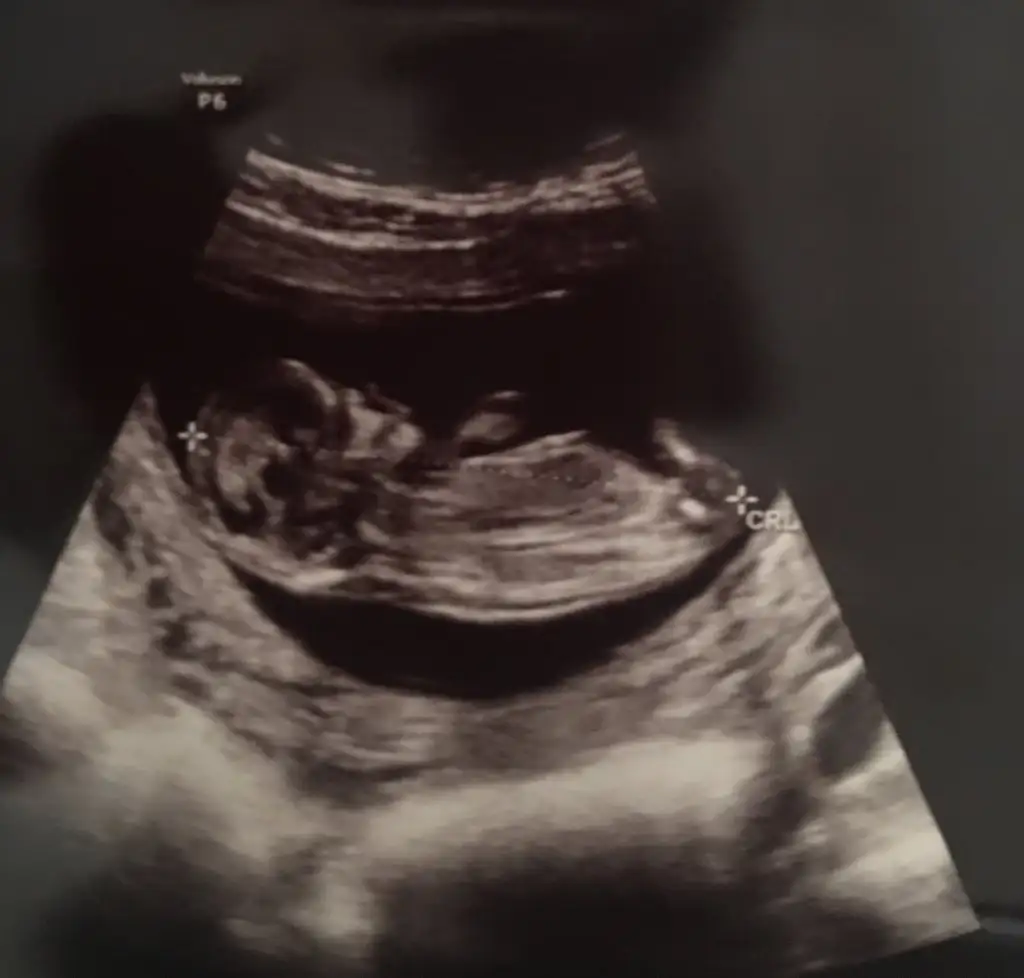

dr soylemeden siz gorun genital nub teorisi ( bebegin cinsiyeti)

Doktor kız tahmininde bulundu ama her gören erkek diyor :)

Evet erkek gibi iri bebek nubta tam dik değil kız yazacaktım .keşke görünüşüne bakmasaymışım 😂😂 saglıkla gelsin prenses 😍

Doktor tam kesin 3 hafta sonra söyleyecekmiş inşallah doktorun tahmini değişmez :)

Önceliğim sağlıklı olması ama kız deyince hemen alışıverdim :))